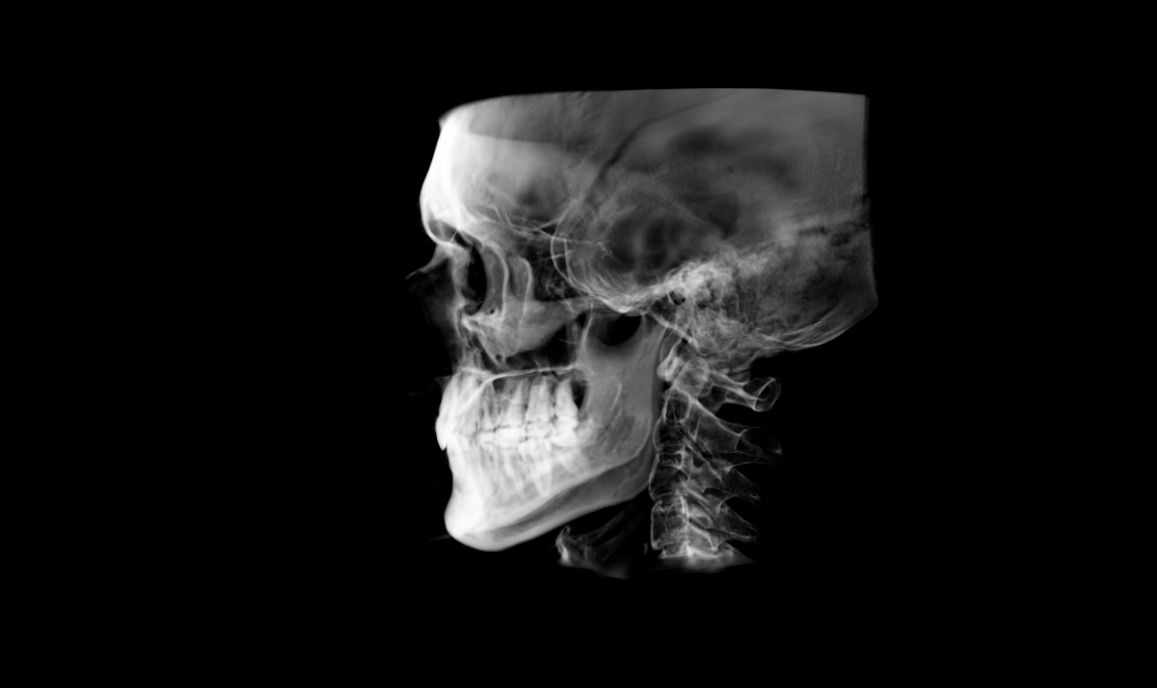

CBCT:

• Head Posture: Forward Head Posture

• Mallampati: Class IV

• Tonsils: Grade 1